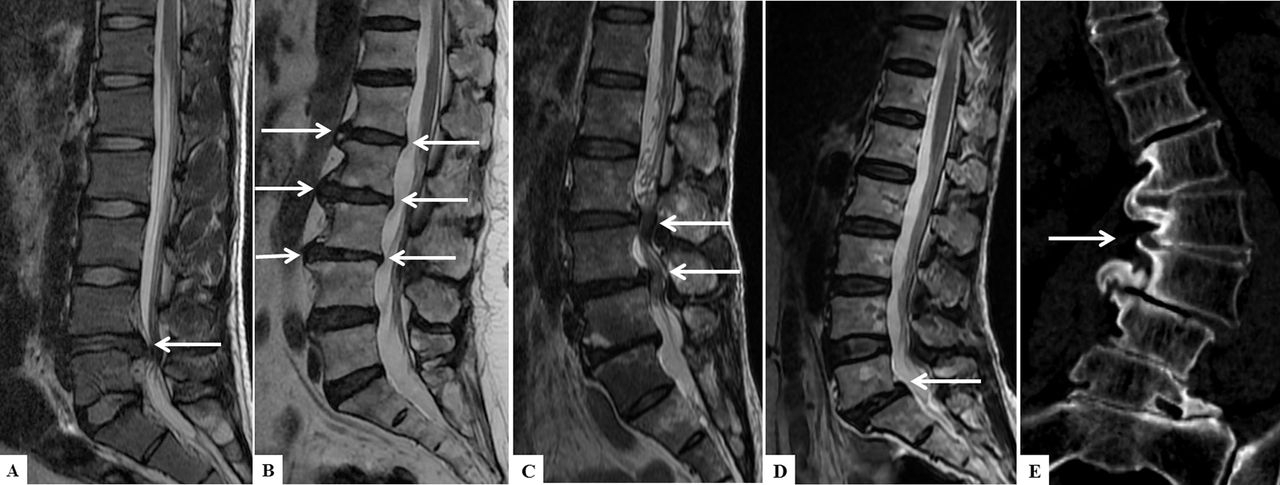

Спондилез поясничного отдела позвоночника - симптомы и лечение

Под спондилезом поясничного отдела позвоночника в современной медицине подразумевают образование между позвонками неких костных наростов-шипов, сужающих позвоночный канал и производящих раздражающее действие на мышцы и связки спины. Эти отрицательные изменения неизбежно приводят к расширению у позвонков нагрузочной площади. В свою очередь, этот фактор способность позвоночника к амортизации любых нагрузок, и заболевание быстро прогрессирует, доставляя все больше дискомфорта пациенту.